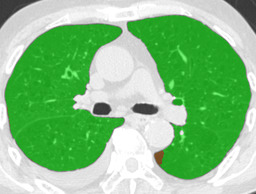

Recall, precision, and dice coefficient (a.k.a F-measure) were used for the evaluation. For the sake of the evaluation, continuous softmax outputs were converted into discrete class labels by selecting the classes that gave the maximum probability. Table 2 shows the evaluated metrics for each method. By paired t-tests, statistically significant differences were confirmed between the proposed method (λ=0.1𝜆0.1\lambda=0.1) and other methods in dice coefficients. As shown in Table 2, utilizing weakly annotated pixels increased precision and λ=0.1𝜆0.1\lambda=0.1 was the optimal value that balances recall and precision in this experiment. Evaluated dice coefficients for the proposed method (λ=0.1𝜆0.1\lambda=0.1) are shown in Figure 2. As shown in Figure 2, even though the proposed method improved the segmentation accuracy, segmentation accuracy varies between slices. Figure 3 shows the confusion matrix of the pixel-wise classification result. In Figure 3, Lweaksubscript𝐿𝑤𝑒𝑎𝑘L_{weak} pixels misclassified as corresponding Lstrongsubscript𝐿𝑠𝑡𝑟𝑜𝑛𝑔L_{strong} (e.g. pixels of lCON¯subscript𝑙¯𝐶𝑂𝑁l_{\overline{CON}} classified as lCONsubscript𝑙𝐶𝑂𝑁l_{CON}) are represented as “Others”. As shown in Figure 3, DLD class combinations with similar texture patterns such as HCM and EMP were misclassified into each other. Figure 4 shows the average result for each DLD class and tested method.

Ground truth Supervised only Proposed (λ=0.1𝜆0.1\lambda=0.1) Proposed (λ=1𝜆1\lambda=1)

EMP \blacksquare

Refer to caption Refer to caption Refer to caption Refer to caption

0.793 0.847 0.815

Figure 4: Average results and dice coefficients for each DLD pattern. Automated segmentation results are superimposed with colors. For each DLD pattern, the slice that gave the median dice coefficient for the proposed method with λ=0.1𝜆0.1\lambda=0.1 was chosen to represent the average result. Note that although CNN performed multi-class segmentation, only one DLD pattern per slice was taken into account for the evaluation.